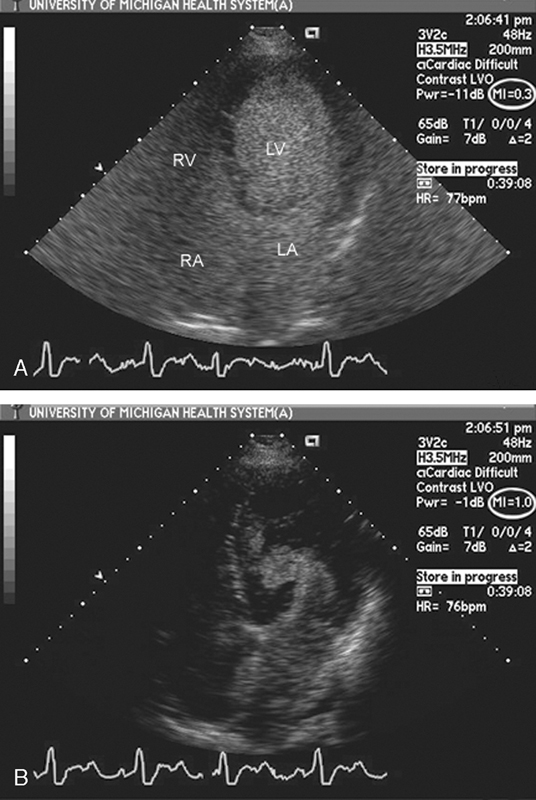

فحوصات تشخيصية لبعض امراض القلب والشرايين التاجية